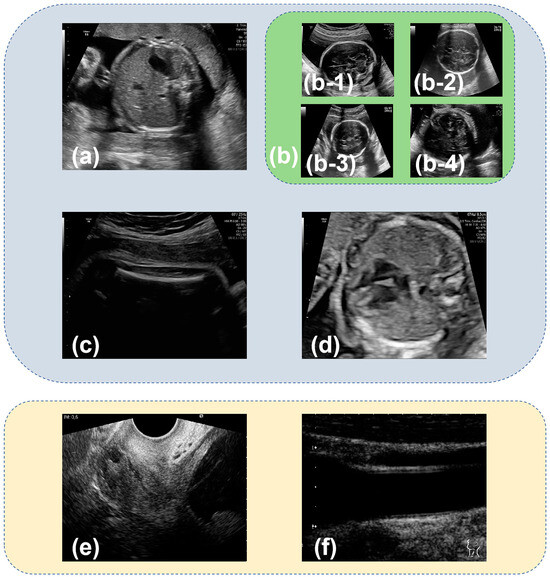

Compared with SonoNet64, the proposed network had a better ability in the detection of the fetal abdomen and fetal thorax standard planes (Figure 4 and Figure 5). To explore the interpretability of the proposed LPC-SonoNet and SonoNet64, the gradient-weighted class activation mapping (GradCAM) [34] technique was used, and the heatmaps generated with GradCAM which used warm color to depict the attention of the network on the input data are shown in Figure 6. The heatmaps of LPC-SonoNet are more concentrated in the relevant regions of the fetal abdomen and fetal thorax standard planes than SonoNet64. It is possible that the pyramid architecture in LPC blocks enable the proposed network to have a large receptive field so that it can focus on the right regions related to the class of standard plane. However, this architecture makes the proposed network ignore the boundary of tissue so that the proposed network performed worse than SonoNet64 in the detection of the outlines of the skull and femur which is important in the classification of brain and femur standard planes.

Figure 6. The comparison of heatmaps from the proposed network and SonoNet generated by the gradient-weighted class activation mapping (GradCAM) [34] technique.